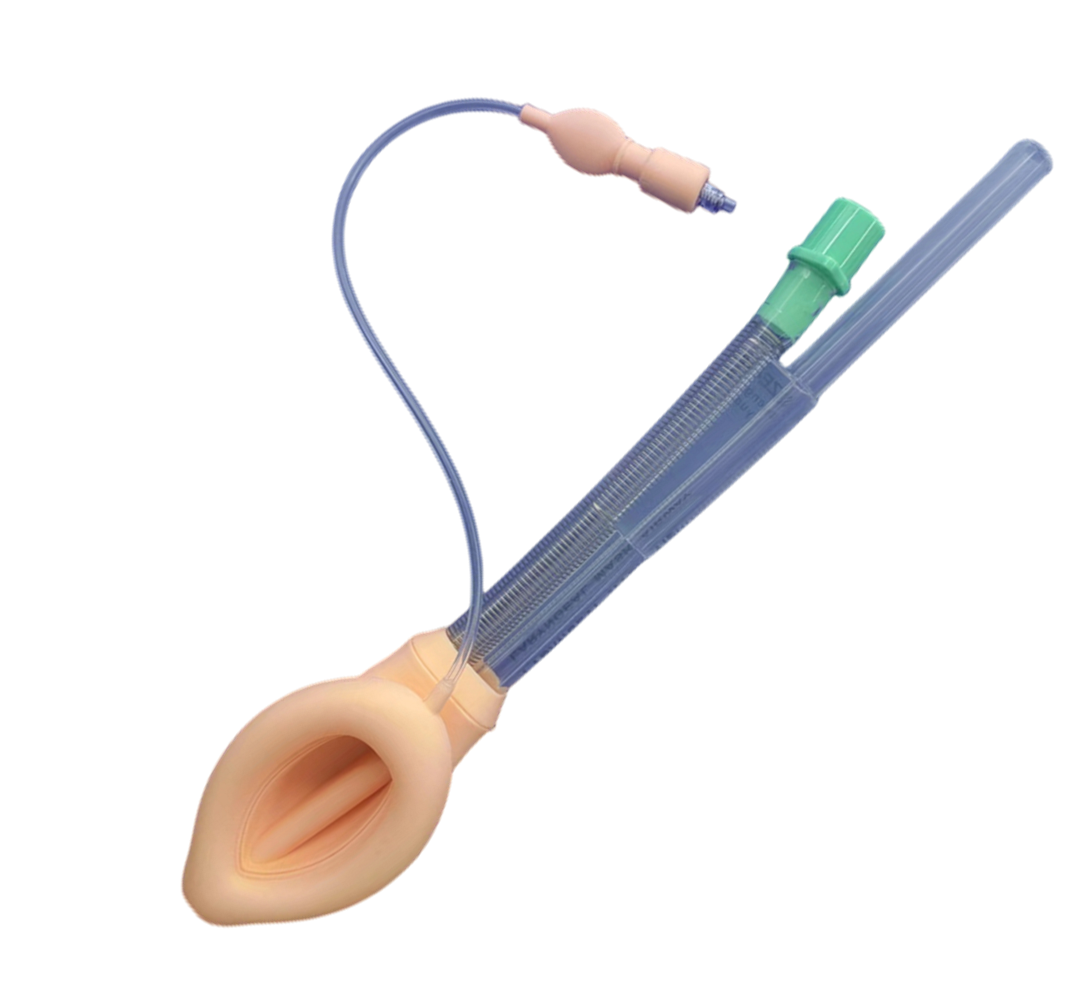

食道引流型喉罩

一次性醫(yī)用喉罩(普通型)